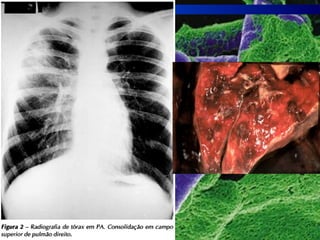

Pneumonia

 A maioria das pneumonias é provocada

pela bactéria Streptococcus pneumoniae.

 Começa com febre alta, dor no peito ou

nas costas e tosse com expectoração.

 O médico deve ser consultado

Pneumonia  A maioriadas pneumonias é provocada pela bactéria Streptococcus pneumoniae.  Começa com febre alta, dor no peito ou nas costas e tosse com expectoração.  O médico deve ser consultado